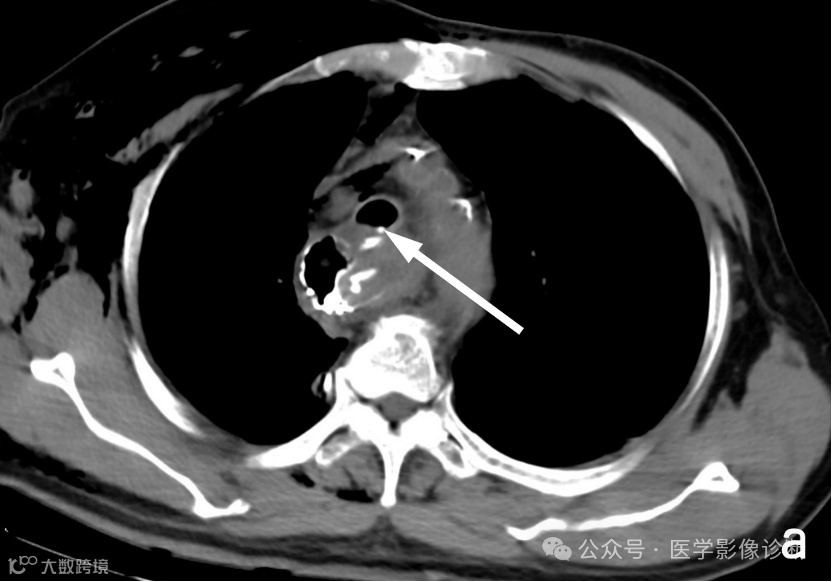

患者,男性,67岁,食管癌术后。

轴位 CT 显示食管癌术后变化(a, b)。然而,由于临床提供的申请表没有提醒,放射科医生只描述了术后变化,没有提及气管食管瘘。多平面成像(MPR)可以更好地显示瘘管。根据口服造影剂的使用情况,放射科医生应该明白医生想要观察是否发生了瘘管。